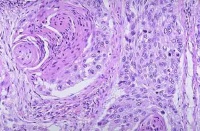

表皮角化,肿瘤由鳞状上皮细胞团块所组成,不规则地向真皮内浸润,棘细胞呈瘤性增生,呈条索状或巢状细胞团,边缘以基底细胞层,中心部有角化性癌珠,在癌细胞团内有很多分裂象,周围淋巴细胞和浆细胞浸润。

鳞状细胞癌可表现角化、角化珠形成和/或细胞间桥等特征。这些特征随分化程度而表现不同。在分化良好的肿瘤中该特征表现明显,而在分化差的肿瘤中仅局部可见。